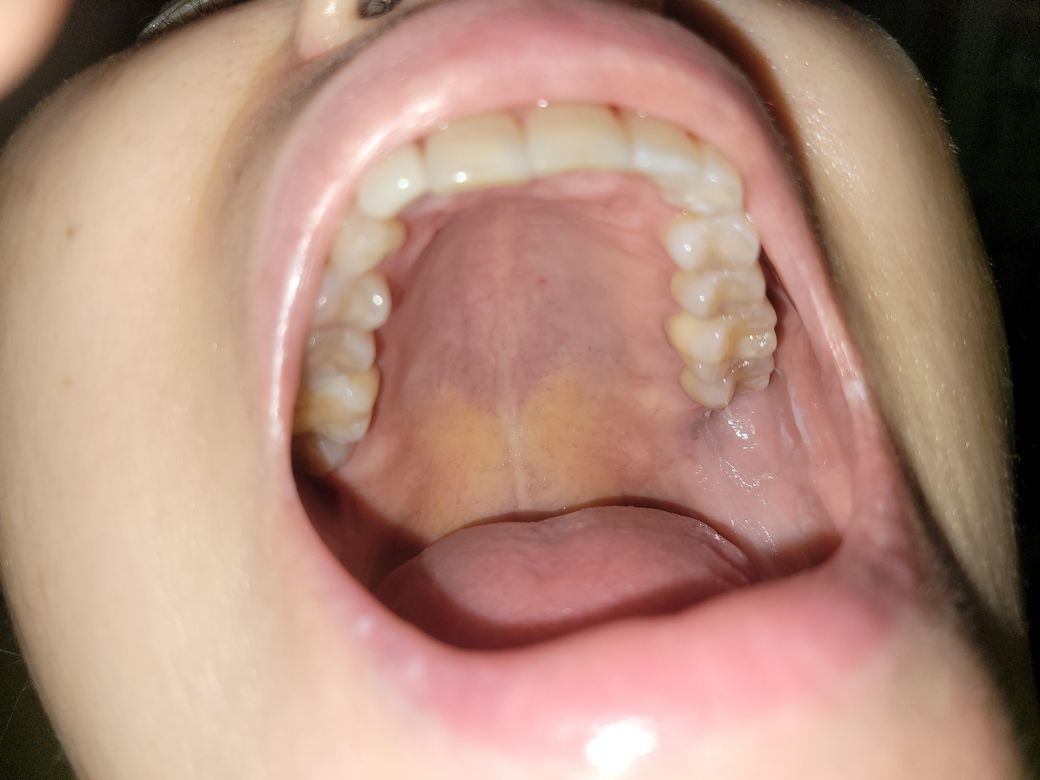

입천장에 노란 나비 모양, 까만 부분 병증2

1. 입천장 나비모양의 노란 부분은 뭘까요? 통증은 없습니다.

2. 치열 왼쪽 끝의 잇몸이 헐어서 알보칠 바르고 있습니다. 그런데 사진으로 까만 부분이 보여요. (사진을 확대하면 보입니다.) 이건 무엇일까요? 걱정됩니다.

입천장은 문제가 잇느건 아니고 다른곳보다 그냥 색상이 저렇게 보이는게 아닐까 생각되고 까맣게 보이는 부분은 치아 뿌리가 남아서 그러는건지 염증이 잇어서 그러는건지는 엑스레이를 찍어보셔야될것같습니다.

1. 입천장은 연구개와 경구개로 나뉘어 있는데요. 해당 부위는 그 경계부위로 색 차이가 날 수 있습니다. 때문에 정상적인 구조라고 생각하시면 되고 걱정하지 않으셔도 되겠습니다.

2. 몸상태나 외부 자극에 의해 구내염이 발생하기도 하며 보통 수일내로 괜찮아지기 때문에 너무 걱정하지 않으셔도 됩니다.

사진만 봐서는 정확히 알기 어려운데요 세균, 곰팡이, 바이러스 감염 가능성이 있습니다 구강내과 진료 받아보세요